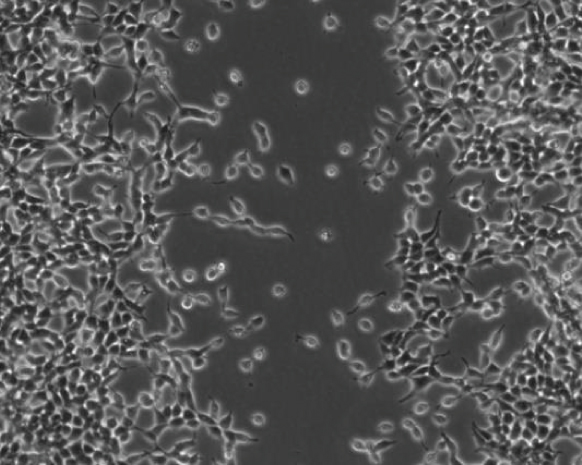

3.5. Wound-Healing Model: Proliferation and Migration

Evidence indicated that metformin suppresses tumor cell proliferation and migration [39–41]. We used a wound-healing model to investigate the effect of metformin on HEK293/TLR4 cell proliferation and migration (Figure 4). The images of the wound-healing model were shown in Figures 4(a), 4(b), 4(c), 4(d), 4(e), and 4(f). Ten distances between the boards of the scratch were measured. The relative distances were expressed as percentage to the distances of the untreated cells (Figure 4(g)).

(a)

(b)

(c)

(d)

(e)

(f)

(g)

The relative distances of the LPS-stimulated cells pretreated with 0, 0.1, and 1 mM metformin were 97.29 ± 8.205%, 110.6 ± 10.75%, and 111.3 ± 6.779%, respectively. No significant difference was observed among those groups of cells. The relative distance of the LPS-stimulated cells pretreated with 10 mM metformin was 158.7 ± 4.323%, exhibiting a significant difference compared to that of the cells treated with LPS only (). Interestingly, the cells treated with 10 mM metformin (only) had a relative distance of 139.9 ± 1.087%, which was significantly different with the cells treated with LPS only (). Accordingly, we concluded that high dose of metformin (10 mM) suppressed either proliferation or migration, or both proliferation and migration of the HEK293/TLR4 cells. However, this inhibitory effect of metformin on the cell proliferation and migration may be independent from the suppressive effect on the transcription factor NF-κB, which required further investigation.